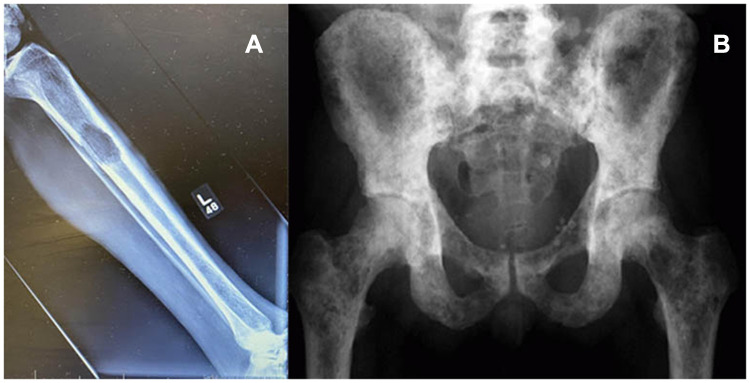

骨骼是转移性疾病的第三大常见部位。治疗很少能治愈;相反,它寻求控制疾病进展和缓解症状。对有转移性骨病症状的患者的影像学评估应从x线平片开始。进一步的成像包括PET -CT扫描和骨显像的结合。我们建议在影像学检查后进行活检。转移性骨病的治疗方法包括全身治疗、放射治疗(RT)和手术。外束放射治疗(EBRT)用于骨折稳定后疼痛控制和术后治疗。单分数和多分数方案同样有效地实现疼痛控制。对即将发生骨折的患者进行充分的骨折风险评估,以指导患者做出稳定骨折的决定。尽管特异性较低,但普通x光片是确定即将发生骨折风险的首选工具。CT扫描具有较高的阳性预测值,可增加诊断价值。手术处理取决于患者的特点、肿瘤类型和骨折/骨的位置。固定选择包括钢板和螺钉固定、髓内钉和内假体。尽管广泛使用,但由于长柄的并发症发生率较高,因此需要对每个患者单独分析整个股骨的预防性稳定。

Bones are the third most common site of metastatic disease. Treatment is rarely curative; rather, it seeks to control disease progression and palliate symptoms. Imaging evaluation of a patient with symptoms of metastatic bone disease should begin with plain X-rays. Further imaging consists of a combination of (PET)-CT scan and bone scintigraphy. We recommend performing a biopsy after imaging workup has been conducted. Metastatic bone disease is managed with a combination of systemic treatment, radiotherapy (RT), and surgery. External beam RT (EBRT) is used for pain control and postoperatively after fracture stabilization. Single-fraction and multiple-fractions schemes are equally effective achieving pain control. Adequate assessment of fracture risk should guide the decision to stabilize an impending fracture. Despite low specificity, plain X-rays are the first tool to determine risk of impending fractures. CT scan offers a higher positive predictive value and can add diagnostic value. Surgical management depends on the patient's characteristics, tumor type, and location of fracture/bone stock. Fixation options include plate and screw fixation, intramedullary (IM) nailing, and endoprostheses. Despite widespread use, the need for prophylactic stabilization of the entire femur should be individually analyzed in each patient due to higher complication rates of long stems.